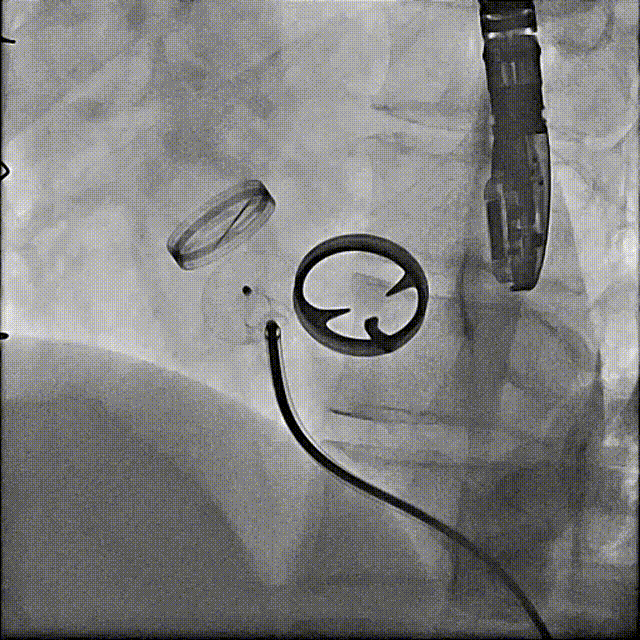

术后封堵器形态位置

手术全程顺利,术中出血100ml,使用造影剂40ml,共计用时1小时50分钟,术后患者无不适,安全返回普通病房,并于3天后出院。